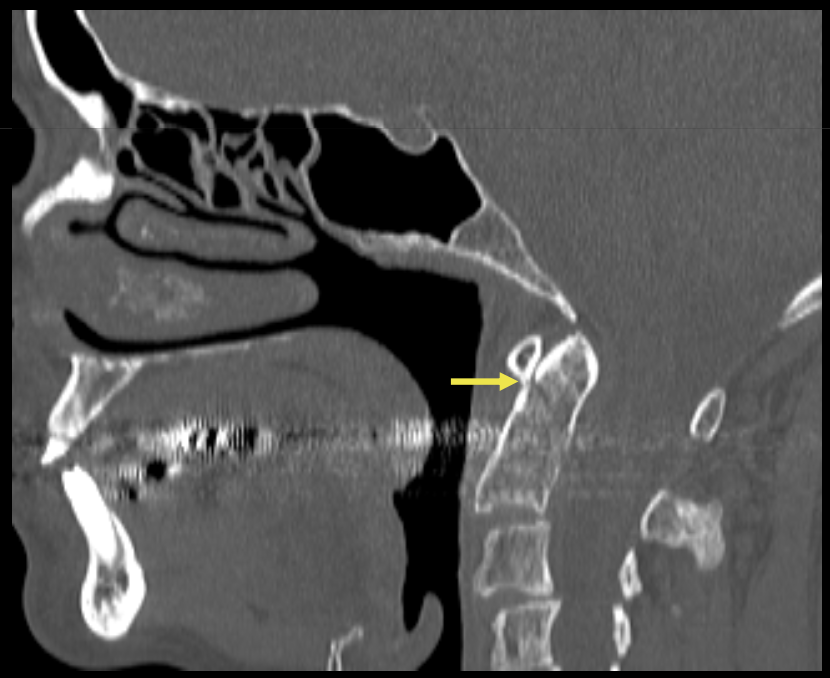

Que regarde-t-on ?

Une dissection carotidienne bilatérale avec une absence d’opacification carotidienne gauche.